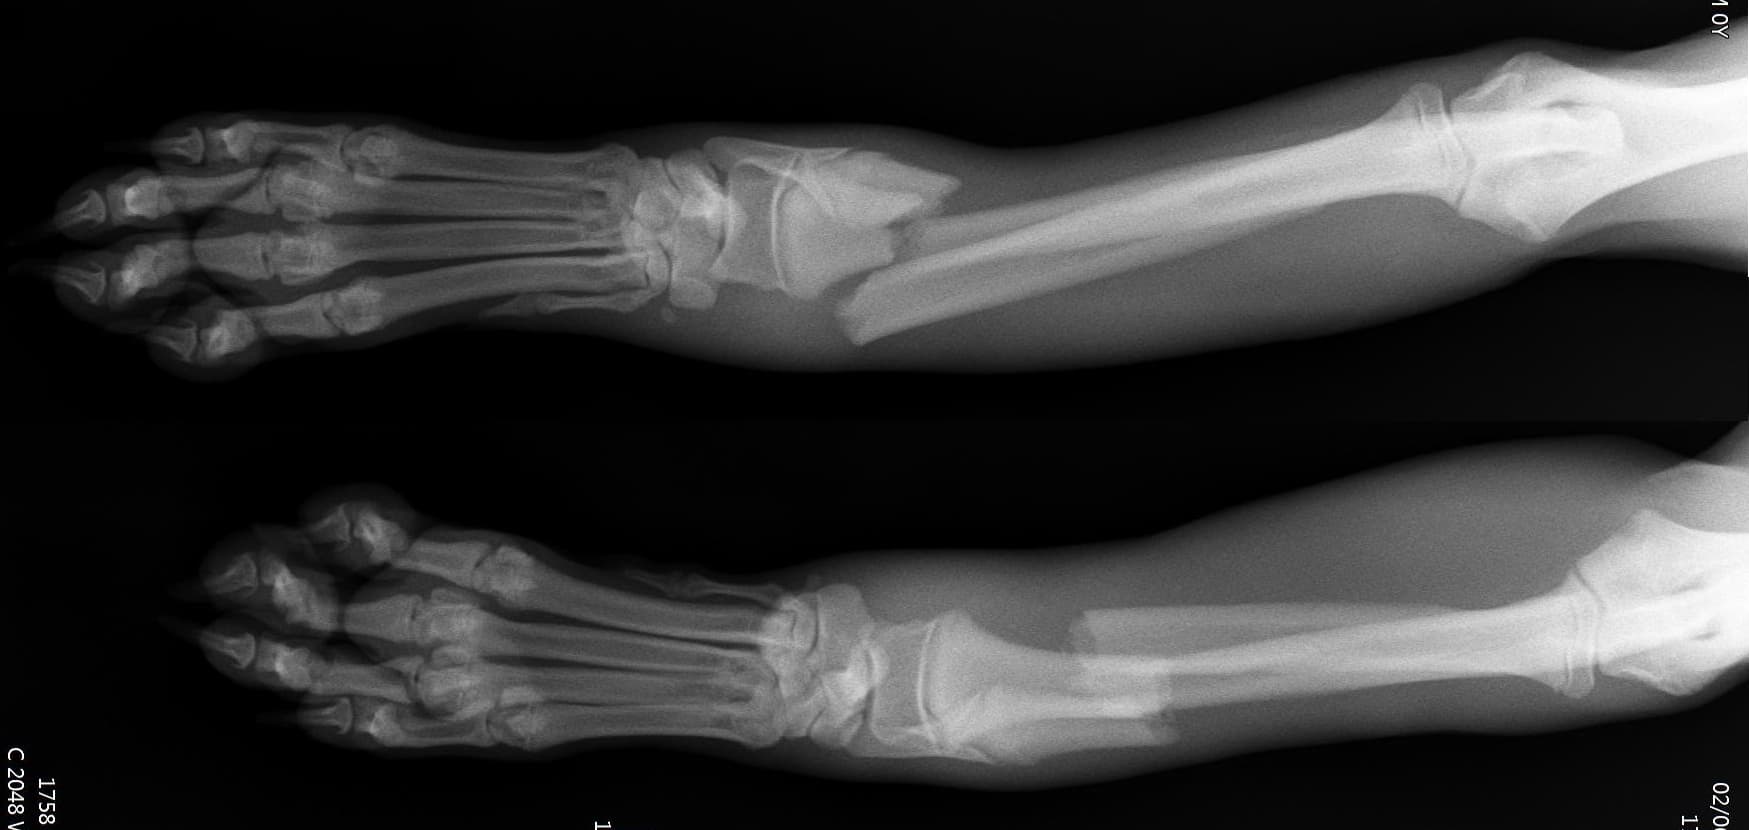

정형외과(Orthopedic Surgery)

정형외과 전공의 수의사가 직접 수술합니다.

호흡마취 시스템과 실시간 모니터링을 통해 안전한 마취가 가능합니다.

환자의 상태를 종합적으로 판단하여 수술을 진행합니다.

수술의 연장선상에 있는 재활 역시 최선을 다합니다.